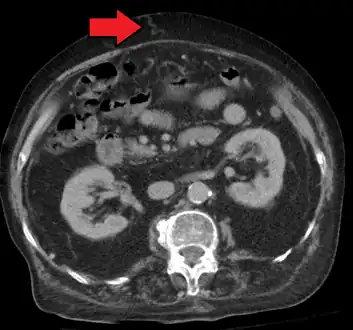

Magnetic resonance imaging of portal hypertension

Portal hypertension due to cirrhosis resulting in revascularization of the umbilical vein

Ultrasonography (US) is the first-line imaging technique for the diagnosis and follow-up of portal hypertension because it is non-invasive, low-cost and can be performed on-site.[12]

A dilated portal vein (diameter of greater than 13 or 15 mm) is a sign of portal hypertension, with a sensitivity estimated at 12.5% or 40%.[13] On Doppler ultrasonography, a slow velocity of <16 cm/s in addition to dilatation in the main portal vein are diagnostic of portal hypertension.[14] Other signs of portal hypertension on ultrasound include a portal flow mean velocity of less than 12 cm/s, porto–systemic collateral veins (patent paraumbilical vein, spleno–renal collaterals and dilated left and short gastric veins), splenomegaly and signs of cirrhosis (including nodularity of the liver surface).[12]

The hepatic venous pressure gradient (HVPG) measurement has been accepted as the gold standard for assessing the severity of portal hypertension. Portal hypertension is defined as HVPG greater than or equal to 5 mm Hg and is considered to be clinically significant when HVPG exceeds 10 to 12 mm Hg.[15]